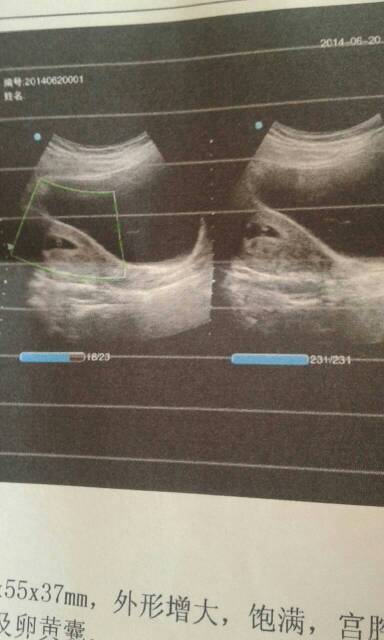

宫体605537!289是孕囊!囊内可探及卵黄囊!约五周加!请问能看得出怀孕多久了? 宫体60✘55✘37!28✘9是孕囊!囊内可探及卵黄囊!约五周加!请问能看得出怀孕多久了? 点击展开 158*****439 2014-06-20 17:17 为您推荐: 其他回答 你好:根据你的报告,的数值,应该符合孕40多天,如有胎芽应该50天 WEIXIANERYUAN 2014-06-20 17:27 相关问题 停经55天做B超:宫腔内探及约1 1*1 1*0 7cm妊娠囊回声,内见卵黄囊,未见胎芽及原始心管搏动,正常吗? 医生您好:产后55天复查,子宫大小为:37*31*28,宫颈厚25,内膜厚6,宫体肌层回声均匀,居中,这个值正常吗? 怀孕34天检查:孕酮4 95HCG74 44怀孕37天检查孕酮6 55 HCG176 6 怀孕39